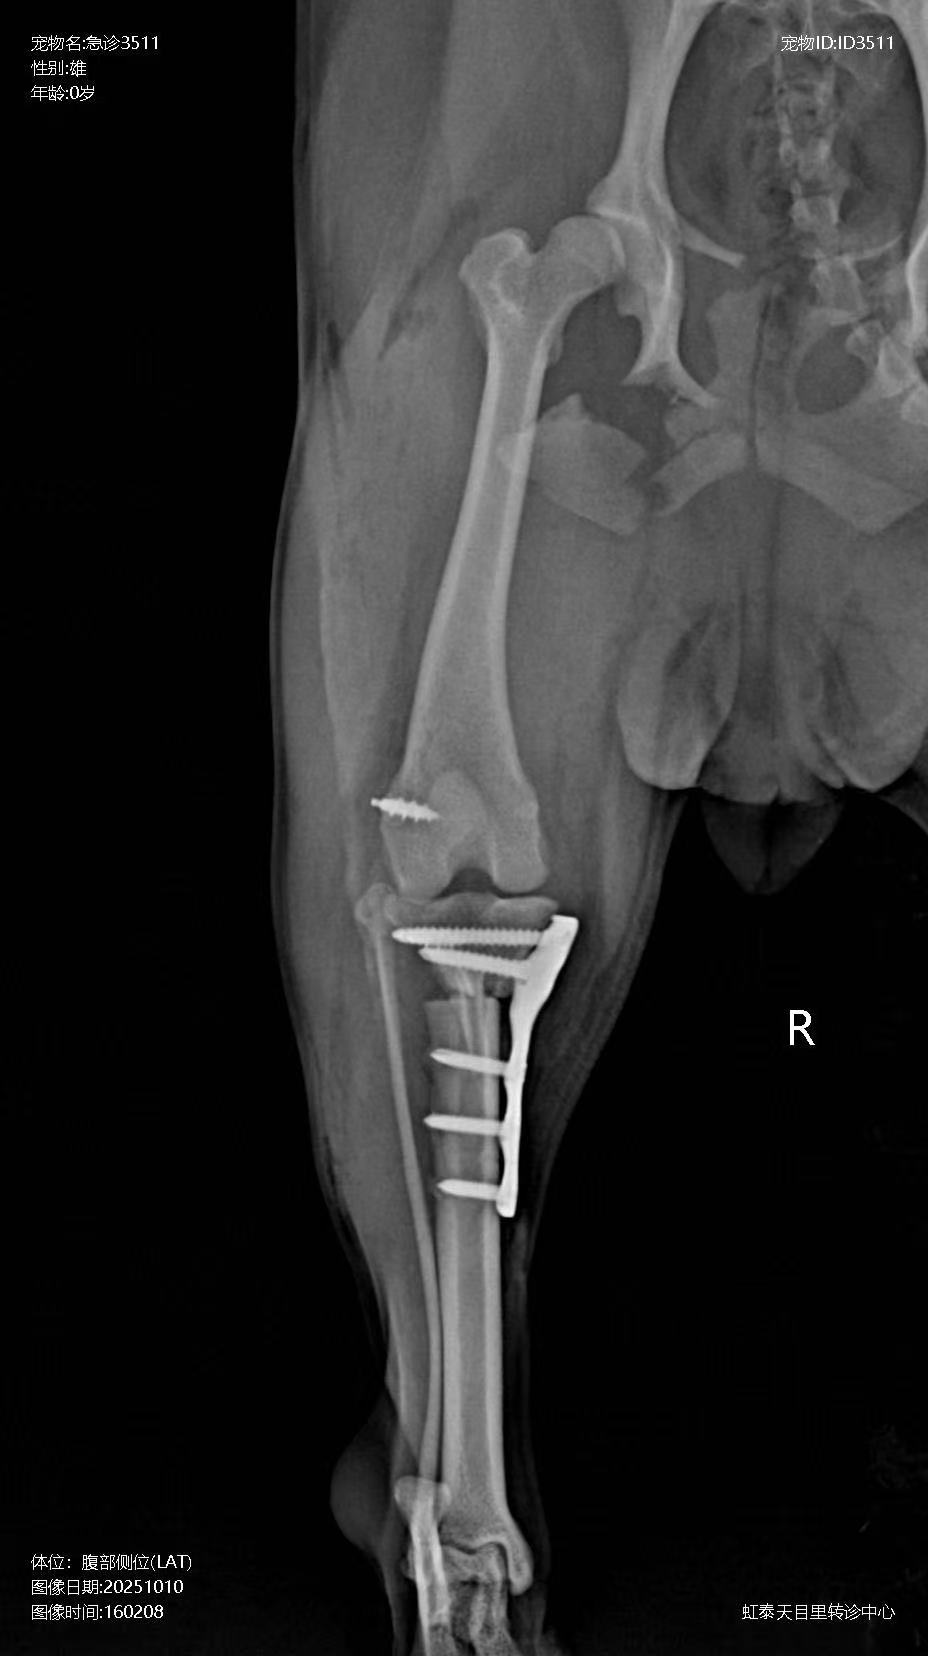

Preoperative X-ray:

Postoperative X-ray